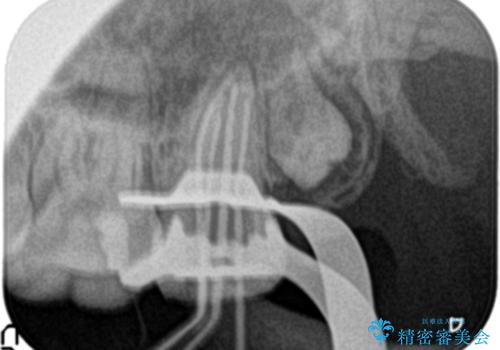

根管治療~フルジルコニアクラウンにて修復しております。

治療前には打診、圧痛がありましたが治療後には症状が消失し、3ヶ月後のレントゲンでも透過像の縮小を認めています。

治療介入時、根管内部にはカリエスや異物が存在する状態でしたが適切な処置を行うことで症状を改善することができました。